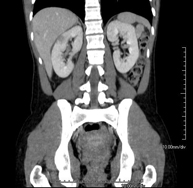

- TC Abdomen

Prueba diagnóstica que consiste en obtener imágenes del abdomen de alta definición anatómica (hígado, vesícula biliar, vía biliar, páncreas, bazo, estómago, intestinos, riñones, estructuras vasculares, vejiga, útero y ovarios, etc.) mediante el empleo de un equipo de TC (Tomografía Computarizada). Dichas imágenes se estudian posteriormente en una estación de trabajo que permite reconstrucciones bidimensionales en diferentes planos del espacio, y también reconstrucciones 3D (volumétricas). La mayoría de estudios requieren el empleo de contraste yodado para mejorar la definición de las imágenes.

- TC Riñones

Prueba diagnóstica que consiste en obtener imágenes bi y tridimensionales del riñón y del sistema urinario de alta definición anatómica mediante el empleo de un equipo de TC (Tomografía Computarizada). Se realiza el estudio antes y después del empleo de contraste yodado en diferentes "fases renales" para una valoración funcional y anatómica (parénquima renal, uréteres, vejiga urinaria, arterias y venas renales, etc.), así como las estructuras adyacentes (vena cava inferior, aorta abdominal, hígado, bazo, etc.). Está especialmente indicado ante la sospecha de lesiones renales, en pacientes con sangre en orina o hematuria, etc.